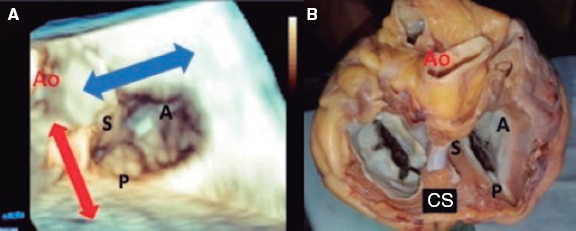

1. Mid-esophageal 4-chamber view at 0º. The septal leaflet (adjacent to the aorta) and the anterior leaflet (adjacent to the RV free wall) can be seen when the transducer is in anteflexion position (figure 1). The posterior leaflet can be seen when it is in the retroflexion position.

Figure 1. A: mid-esophageal 4-chamber view showing the septal leaflet and the anterior leaflet. B: imaginary view in the 4-chamber view. C: deep transesophageal view. A, anterior; TEE, transesophageal echocardiogram; S, septal; CS, coronary sinus.

To optimize the images of the right heart structures, the transducer should be turned clockwise. The artifacts of the septum and aortic or mitral valves can block the view of the septal leaflet. Tricuspid annulus is measured in this view with open flap-like cusps at the end of the diastole.

3. Deep esophageal 4-chamber view at 0°. Since the right inferior border of the heart is close to the diaphragm, the deepest insertion of the TEE transducer reaches the distal esophagus, close to the gastroesophageal junction; it may be that this view will only show the right atrium and coronary sinus and no images of the left atrium (figure 1). This prevents left heart structure-related artifacts from happening like the acoustic shadowing that the mitral prosthetic material can cause on the septal leaflet. This is the optimal view to acquire 3D volumes.

The impact of 3D images is not as powerful when performing procedures on the TV compared to the mitral valve. Lang et al.12 suggest a standard image visualization to see a frontal view of the TV by placing the septal leaflet in the inferior position (at the 6:00 hour position). These recommendations were established at the end of the last decade when there were no transcatheter procedures and the surgical view was trying to be replicated. Rotating the image 90° with the aortic valve in the 11:00 hour position is currently the preferred option. This should improve our understanding of the anatomy of the TV by creating a common language between cardiac imaging specialists and interventional cardiologists.

The quantitative analysis of leaflets and annulus is performed through multiplanar reconstructions of 3D views.13 By placing orthogonal views on the tricuspid annulus at the leaflet insertion site, the TV short axis is acquired. After precise adjustment the annular diameters and area dimensions can be obtained (figure 1 of the supplementary data).

5. When the clip remains perpendicular on the TV, the GC clockwise rotation will move the clip towards the septal position. The GC counterclockwise rotation will move it towards the lateral region. The stabilizer advancement will bring the clip closer to the A-S commissure. After retraction, it will pass to the P-S commissure. This will allow complete range of motion and guarantee the correct location of the grasping (figure 5).

Figure 5. A: transesophageal echocardiogram in 3D zoom mode; periprocedural frontal view. The guide catheter can move inside the right atrium towards the aortic valve by advancing the entire system (red arrow) or towards the posterior leaflet by retracting it; the movement towards the septum (blue arrow) is possible through clockwise rotation of the guide catheter, and towards the right ventricle free wall through counterclockwise rotation. B: explanted heart, anatomic view. A, anterior; Ao, aorta; P, posterior; S, septal; CS, coronary sinus.